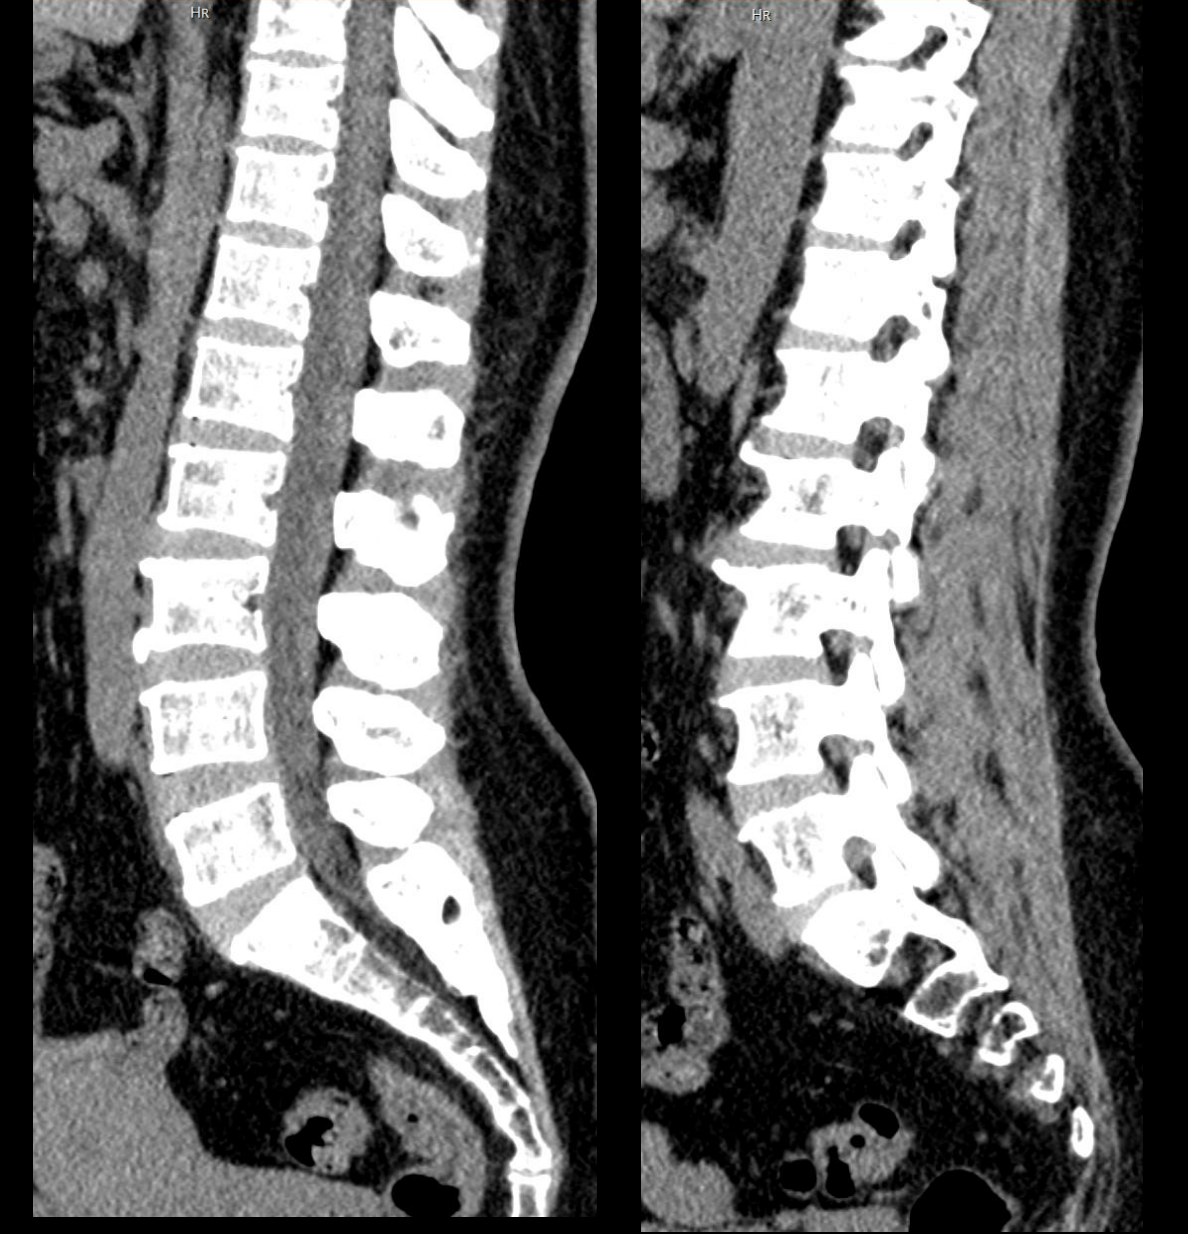

- Giải pháp chẩn đoán hình ảnh mô mềm tiên tiến cho khảo sát ổ bụng

- Tối ưu chất lượng hình ảnh chẩn đoán và giảm phơi nhiễm bức xạ

- Hỗ trợ đánh giá an toàn cho bệnh nhân

- Đảm bảo chất lượng hình ảnh chẩn đoán cao